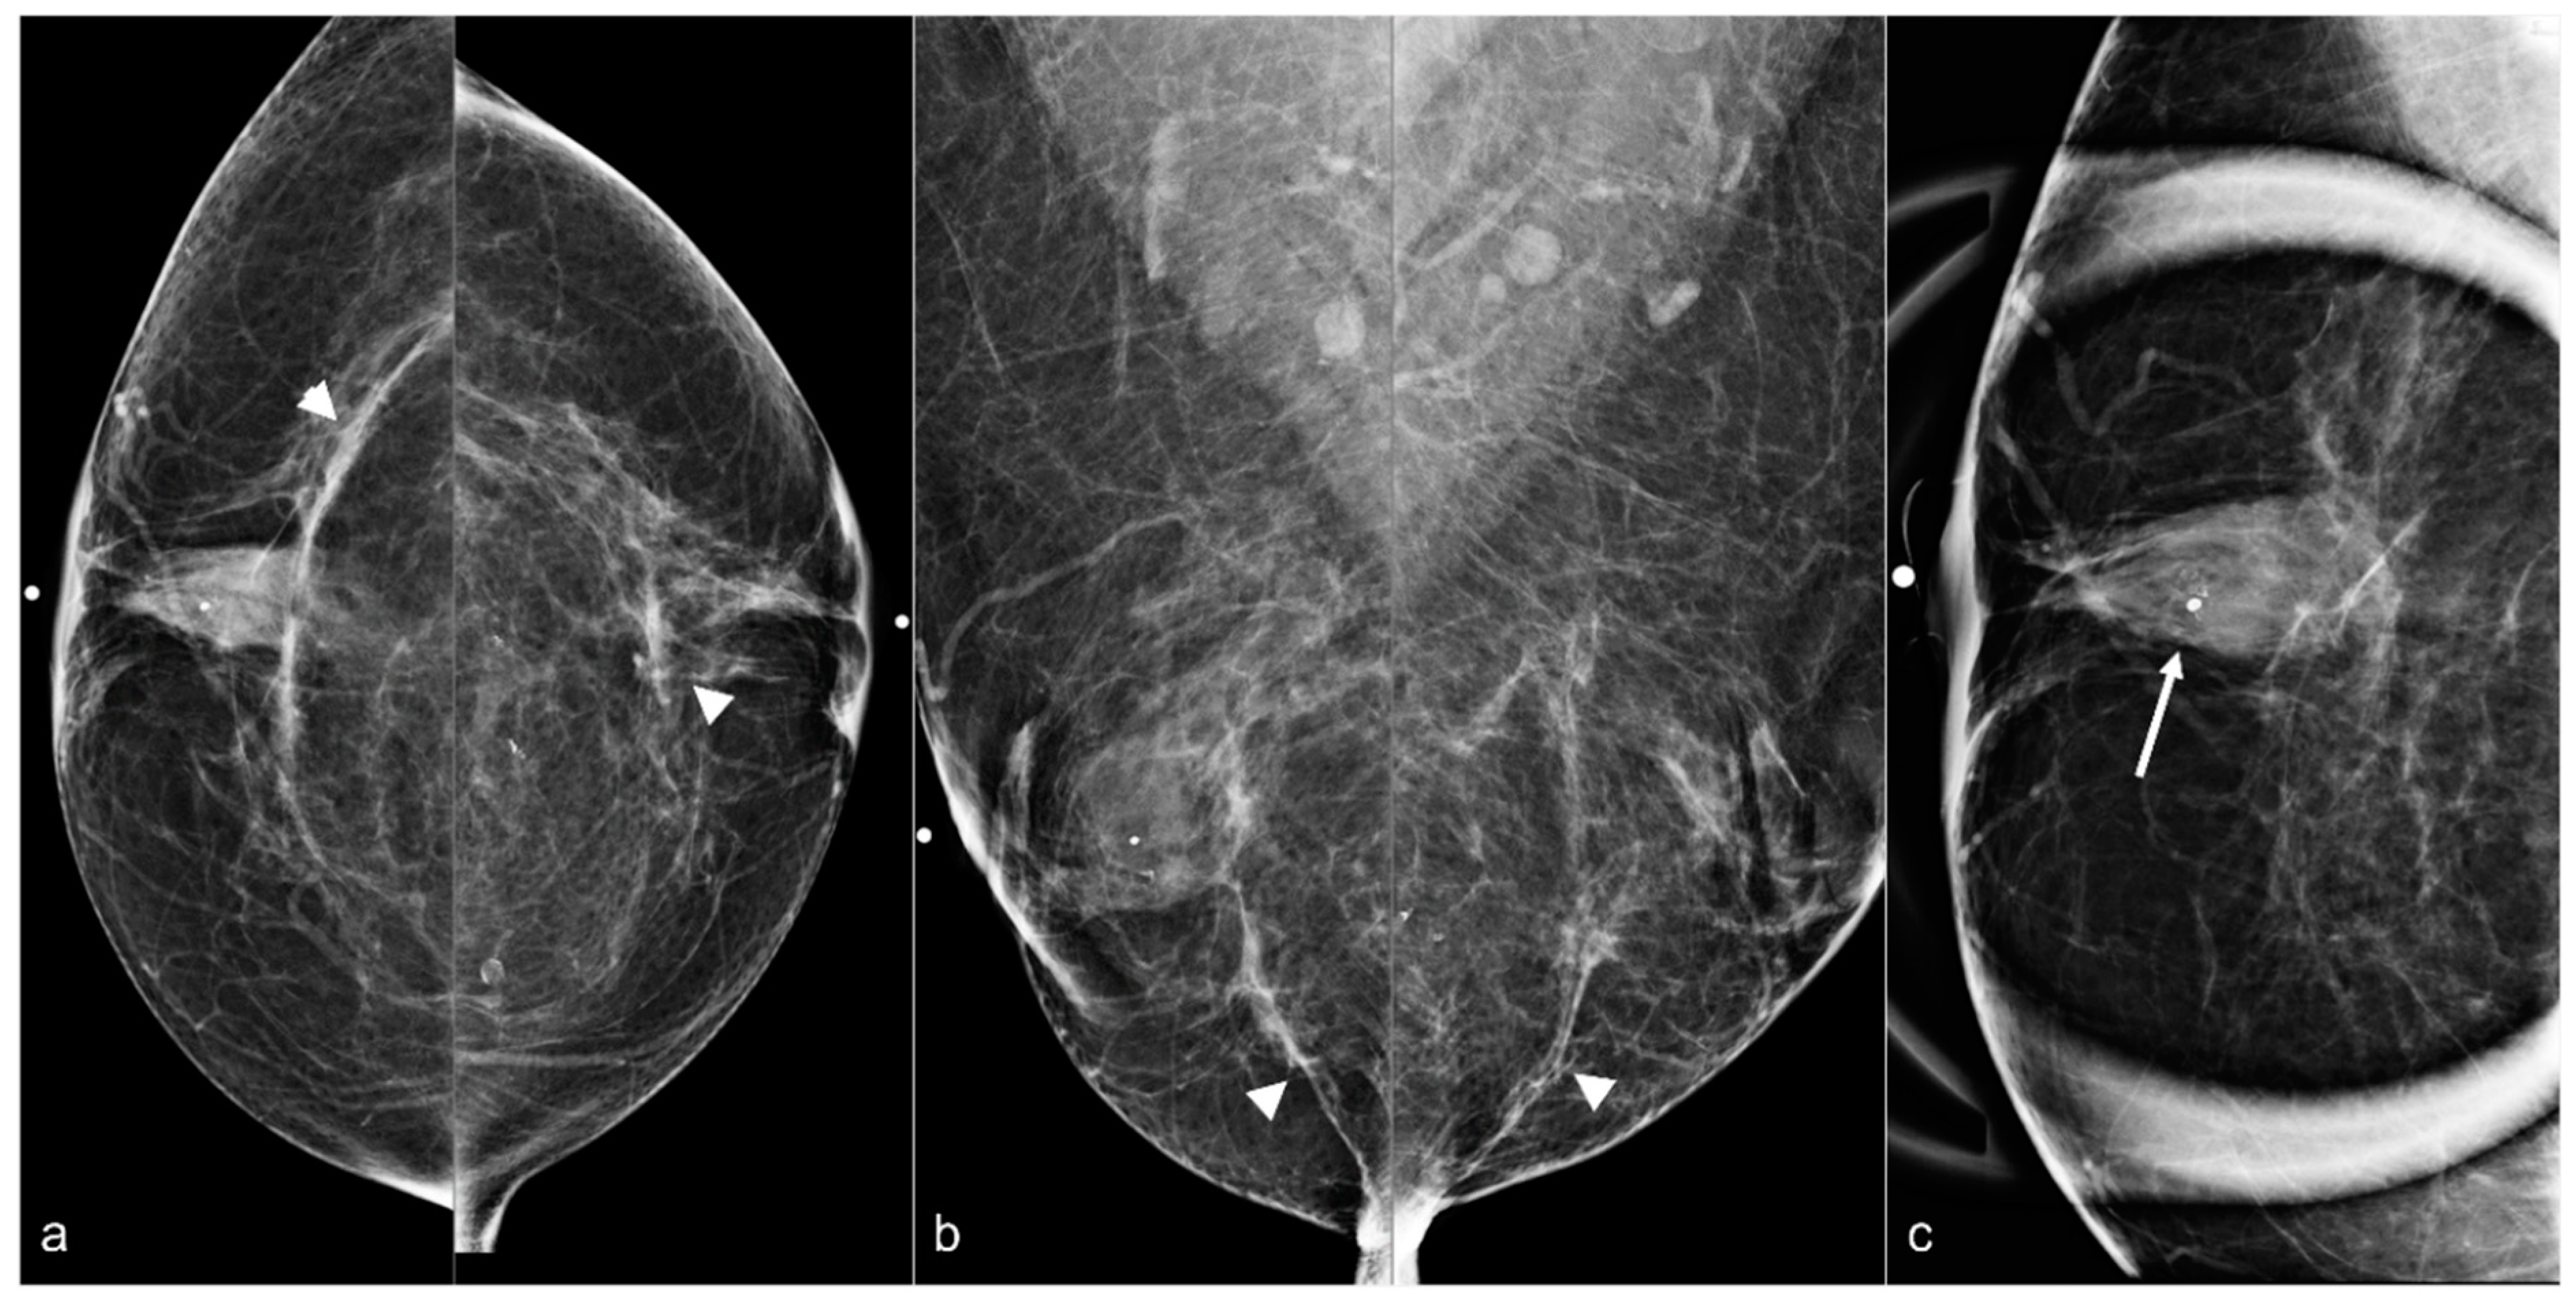

Figure 6. A 58-year-old woman with a history of subglandular silicone implants. BES was performed 1 year before the current mammogram. Bilateral CC (a) and MLO views (b) demonstrate bilateral linear densities indicating fibrous capsules (arrowheads) and bilateral, right greater than left, retroareolar focal asymmetries related to BES. Grouped amorphous calcifications (arrow) seen on a magnified CC view (c) in the right breast retroareolar region were biopsied with stereotactic guidance, with pathology demonstrating fat necrosis and giant cell reaction.